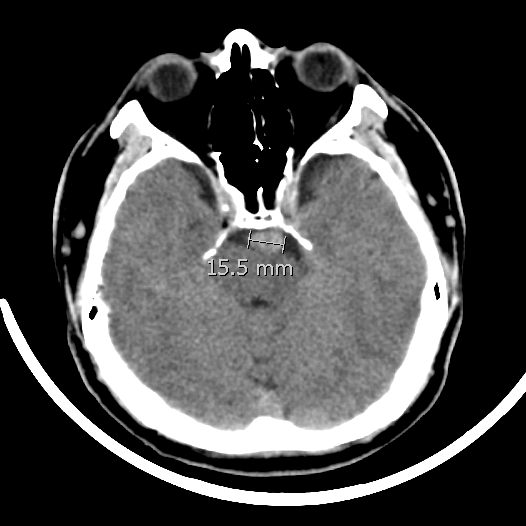

患者男性,34岁,年前自新疆坐车48小时来到我院,诊断:椎基底动脉冗长扩张症,出现脑干压迫症状、后组颅神经症状、部分中组颅神经症状、小脑症状、颅内压增高(220mmHg),症状进行性加重,最大径15mm,血管外面存在血栓造影只能窥见部分,短短两周,病变形态出现明显变化,局部出现明显瘤样凸起(图2-3),手术方案只能临时改变,植入血流导向装置,术后看病人语言、四肢活动均正常,围手术期仍然是一个艰巨的过程,充满了不确定因素,希望患者能安全度过围手术期,早日康复,重返工作岗位~~~